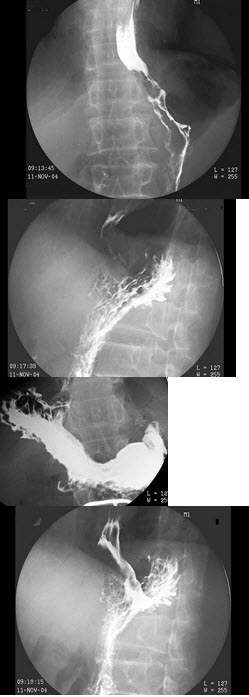

150、单项选择题

男,59岁,进行性吞咽困难半年,结合图像,最可能的诊断为()

A.正常食管

B.食管静脉曲张

C.食管平滑肌瘤

D.食管癌

E.贲门癌侵及胃底、食管下段